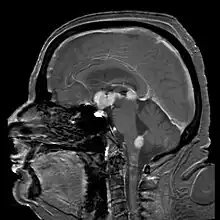

Brain magnetic resonance imaging showing primary central nervous system B-cell non-Hodgkin lymphoma of the sella turcica and hypothalamus, continuing to the tectum (intensely white areas in the middle).